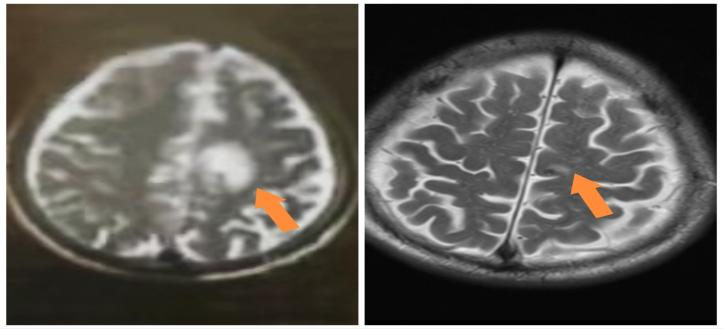

患者男,79岁,2025.5月以“右下肢无力1月”为主诉入院,检查头MRI+C:左侧额叶异常强化,周围片状水肿信号,符合转移瘤;肺CT+C:右肺上叶纵隔旁肿物,可疑恶性。行肺穿刺活检病理诊断为肺腺癌伴少数鳞状分化,免疫组化PD-L1(22C3)TPS=70%,基因检测:KRAS G12V突变,临床分期:cT2aN0M1b IVA期,PS评分1分。恰逢依沃西单抗单药获国家药品监督管理局批准于PD-L1表达阳性(PD-L1 TPS≥1%)的局部晚期或转移性非小细胞肺癌的一线治疗适应症,2025年6月行依沃西单抗单药治疗4周期后患者右下肢无力症状明显缓解,10月复查头增强MRI额叶周围水肿带消失,疗效评价持续PR,治疗期间出现不良反应为恶心呕吐II级,对症止吐治疗后好转,目前持续治疗中。

依沃西单抗4周期疗效对比